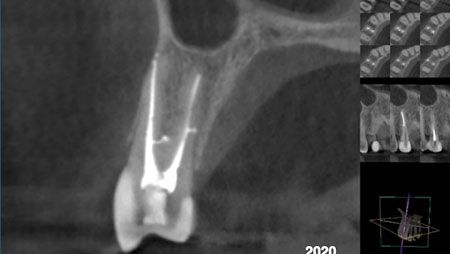

Dens invaginatus, also known as dens in dente, is an embryological anomaly that occurs during tooth formation. The condition results in invagination of the amelodental structure within the pulp that can look like a ‘tooth within a tooth’ on radiographic evaluation, hence the nomenclature.1 The reported prevalence of adult teeth affected with dens invaginatus is … Read more